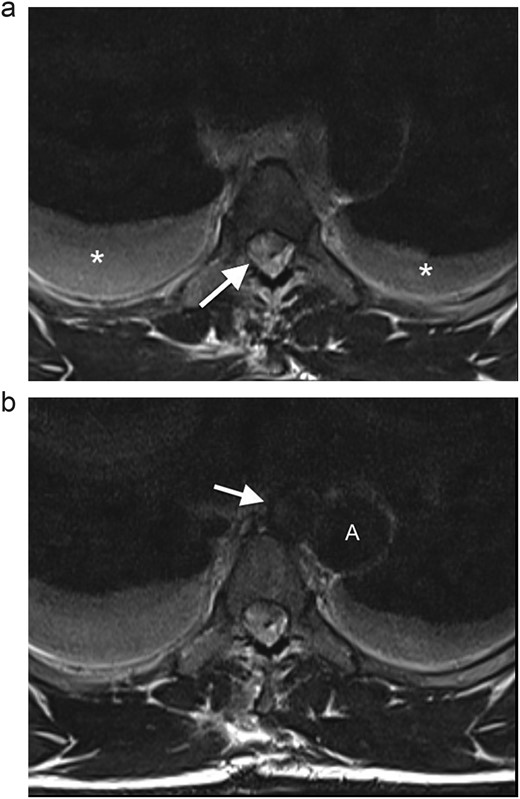

(a) Axial T2WI MR at the midthoracic level demonstrates an epidural hematoma in the right lateral spinal canal with compression of the cord (arrow) and bilateral hydrothoraces (*). (b) Axial T2WI MR shows a round lesion (arrow) inseparable from the medial aspect of the mid-thoracic aorta (A), with an isointense signal to the thoracic aorta.